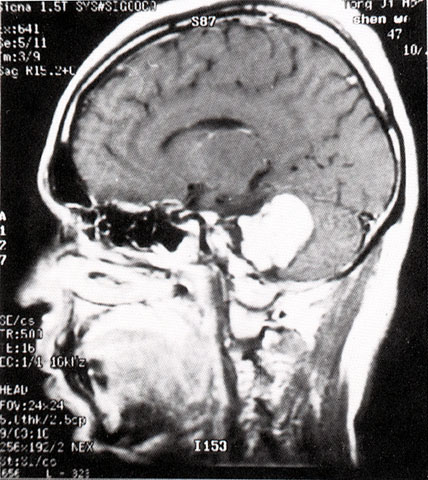

FH1069 听神经病(MRI)

光盘检索编码 FH1069  函授作业图编号 1069

图  名 听神经病(MRI)